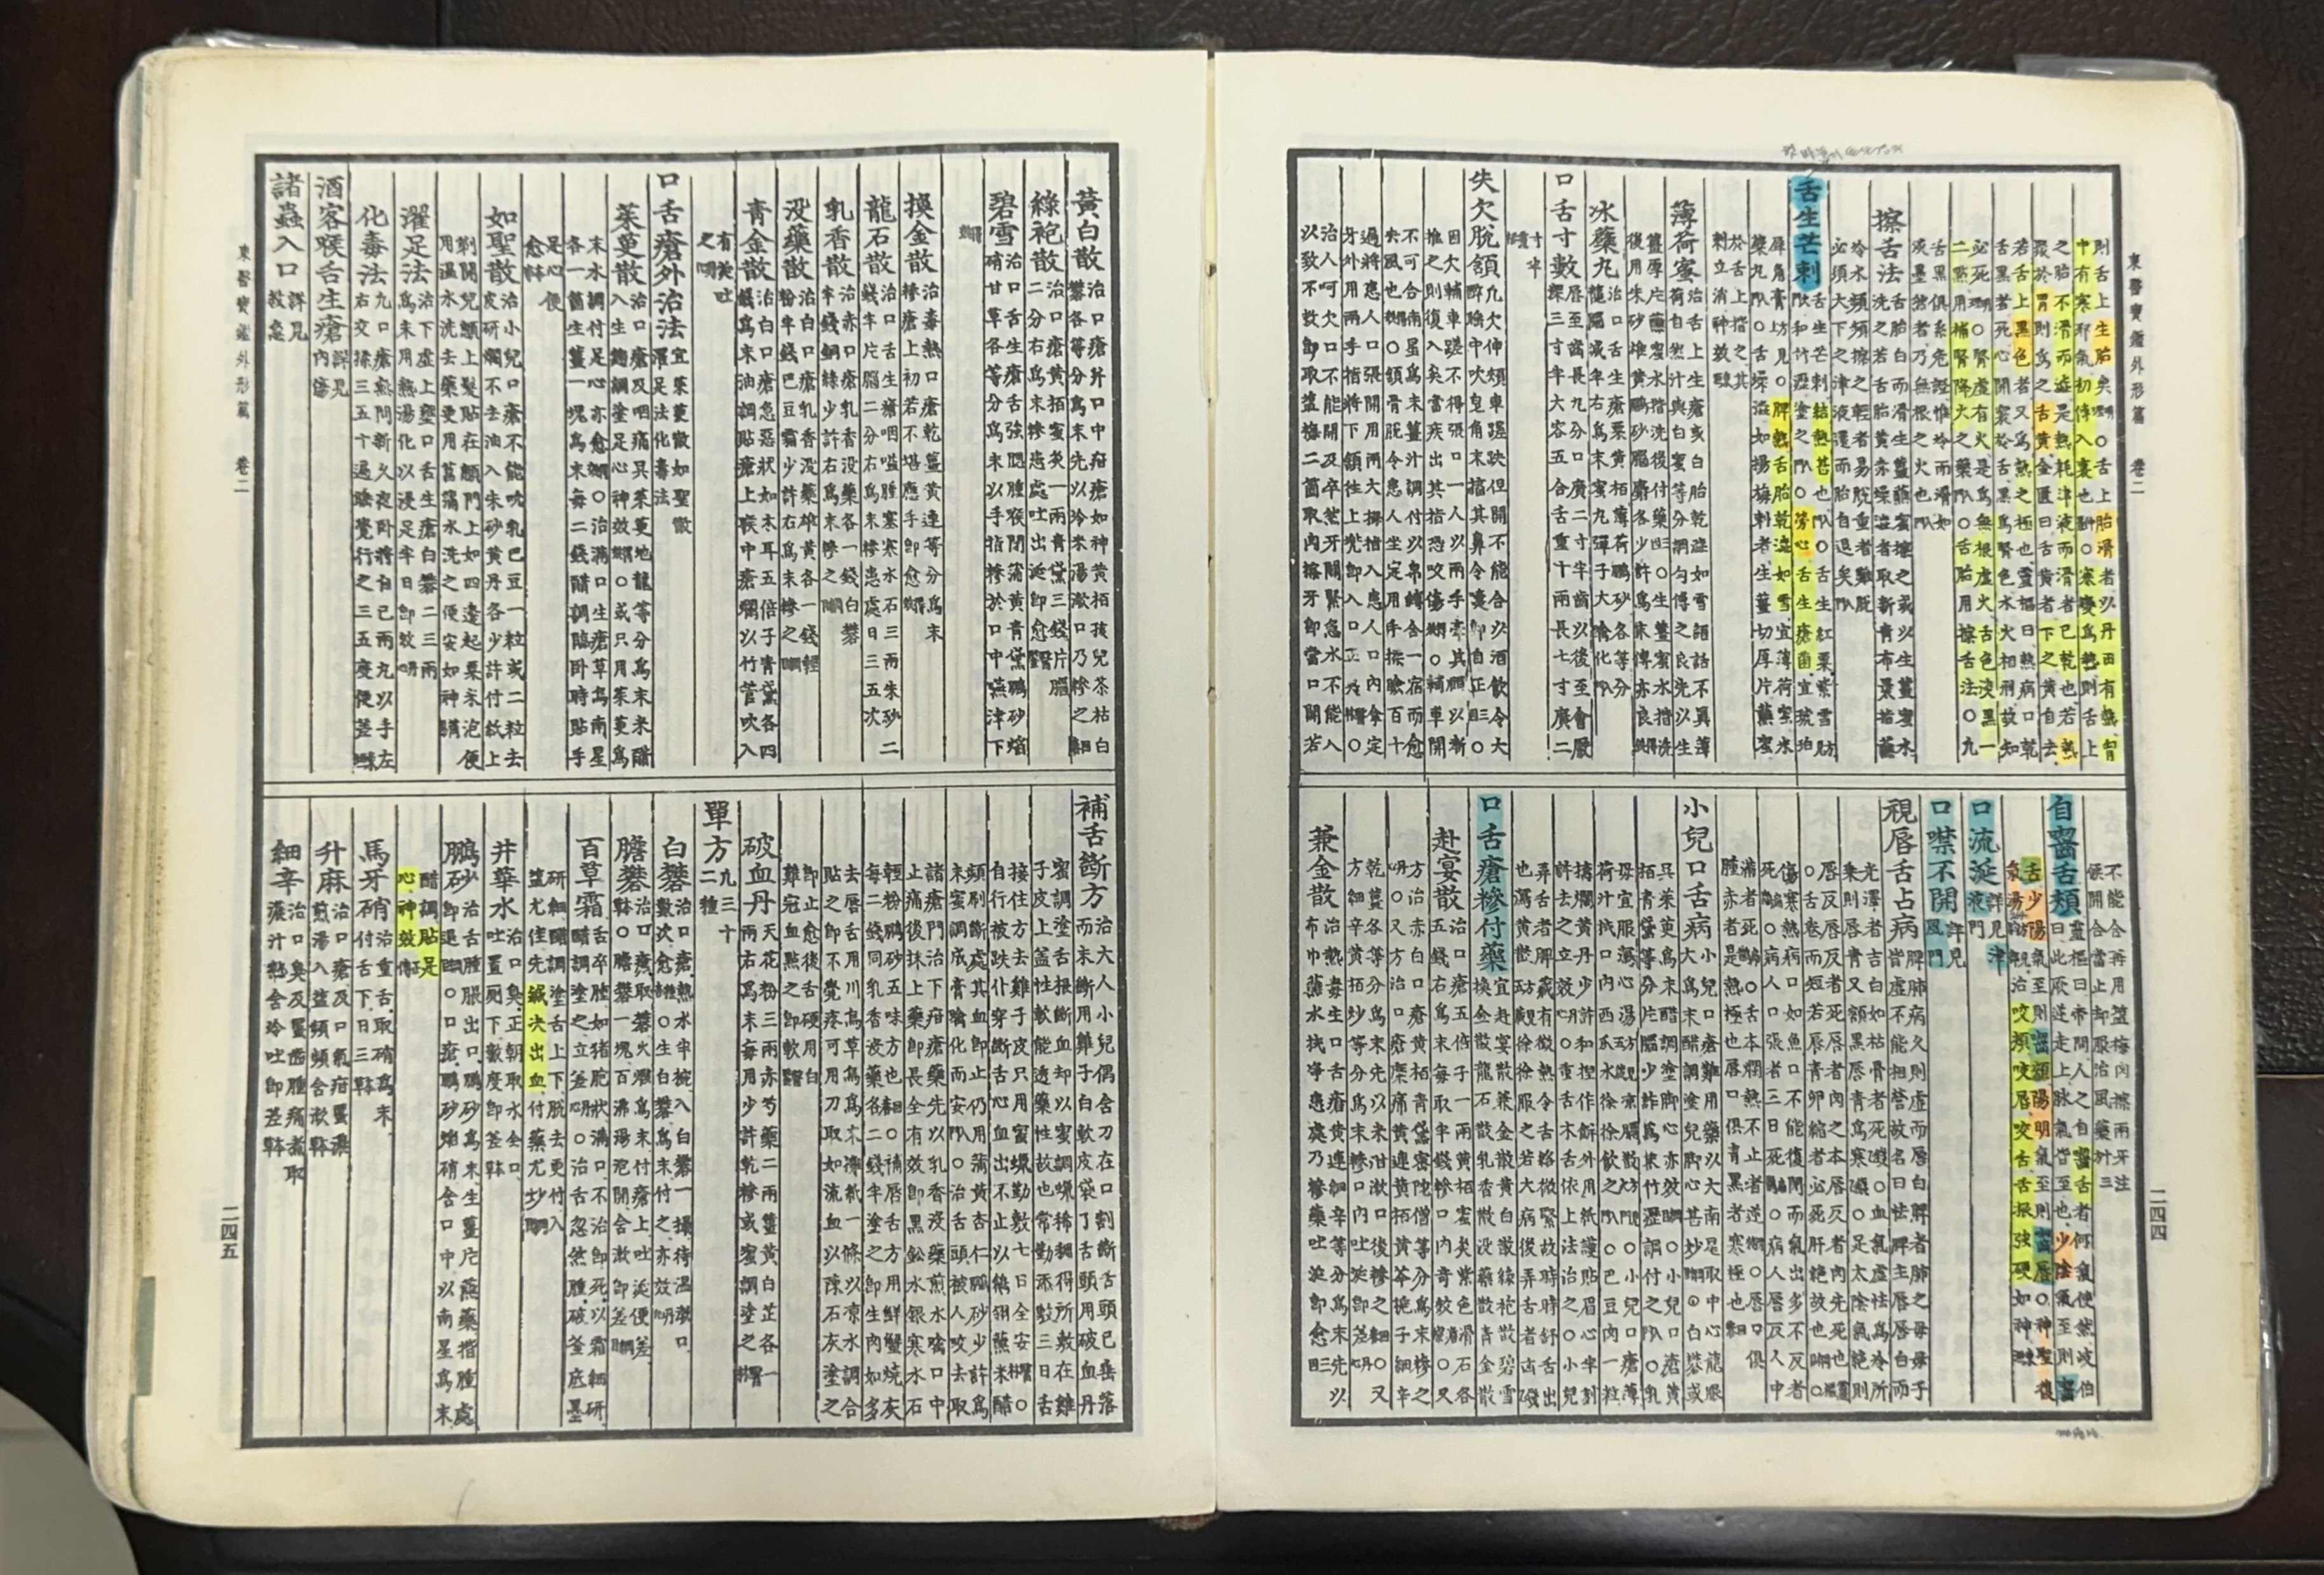

从400年传统的《东医宝鉴》中发现

在中医世家

代代秘密传承的配方 就是这样。

这不是演绎出来的图片。

是真正使用的《东医宝鉴》